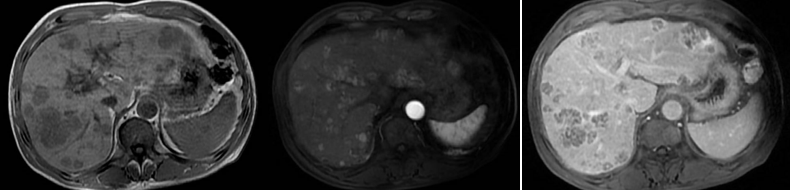

2020年2月27日上腹部CE-CT:考虑肝内多发肿瘤;肝硬化、门脉高压、脾大;增强CT提示:肝内多发肿瘤(符合原发性肝癌快进快出的影像学特征)(图1)。

图1.2020年2月27日上腹部CT